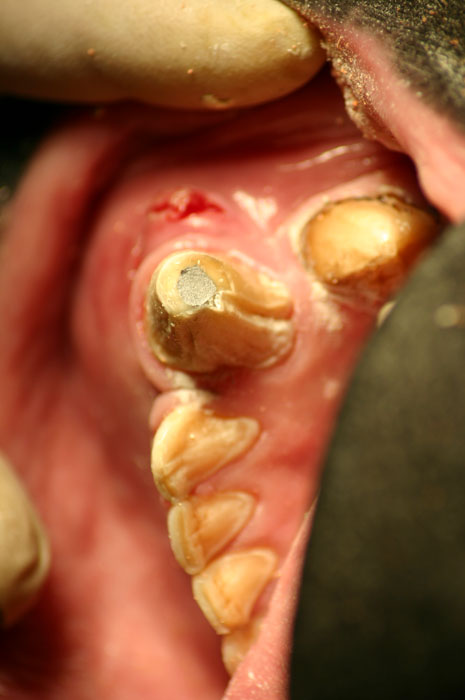

The Large Volume Veterinary Endodontic Syringe™ is an endodontic syringe developed by Dr. John Scheels specifically for veterinary use in all species for complete and consistent obturation of root canals over 30mm long or with large pulp chambers.

It permits the positive deposition of endodontic sealer and filler pastes at the apex of these long teeth. NO SPECIAL NEEDLES are required as it may be used with any standard size hub. Plastic, metal, threaded or non-threaded needle hubs will seal well on the tapered syringe nipple.

Mix enough paste to more than fill the canal and chamber. A 2" or 3" 18 gauge needle is a good choice for reaching the apex of the root canal in cases such as large canid or felid cases.

Fill the needle hub with paste. Attach the hub to the syringe and thread on the needle. Either plastic or metal, threaded or non-threaded needle hubs will seal well on the tapered syringe hub nipple. Place the plunger into the syringe and engage the threads. Turn the plunger to extrude the paste from the needle.

After drying the prepared canal, fit the master gutta percha cone in the canal. Place the needle into the canal all the way to the apex. Turn the plunger slowly and withdraw the needle as the root canal and chamber are filled with paste. Gutta percha points may also be used to aid in condensation and complete obturation as desired. A firm base should be placed over the fill, such as zinc phosphate cement. Then a final restoration material of choice is placed.